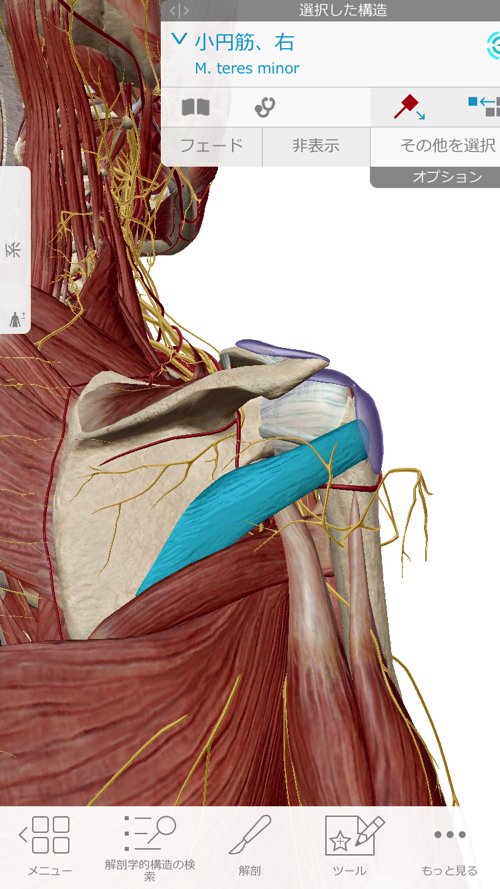

肘がネジレるとこんな感じで繋がっている肩や肩甲骨の位置にずれが生じます。

脇の周りの筋肉も硬直していて腕が上がらない、回せない

動かすと痛い症状を作っていました。

それらの筋肉や腱をすべて緩めて正しい位置に戻したら

痛みが消えてスムーズに動かせるようになりました。